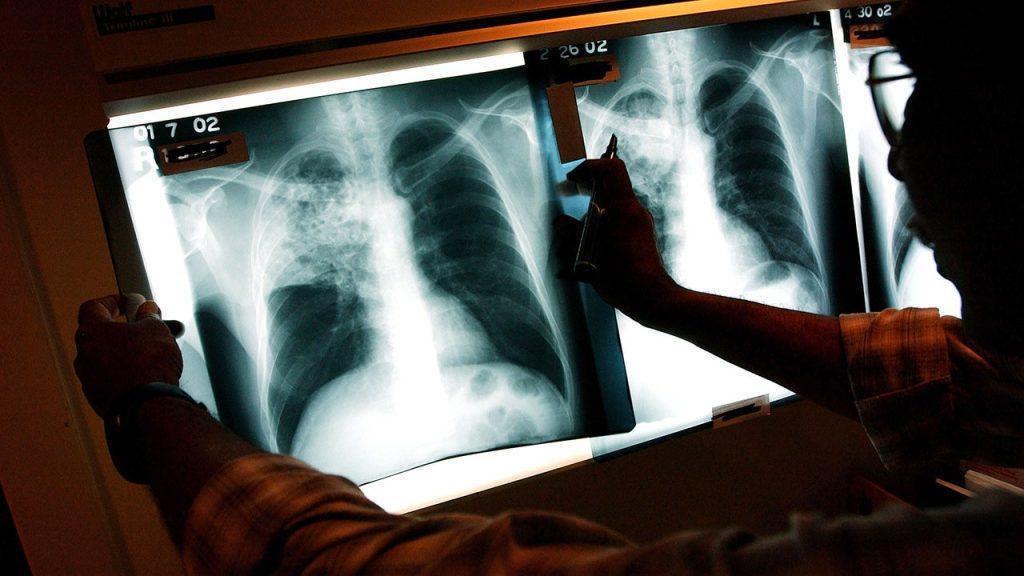

TB, primarily targeting the lungs, spreads through the air and can be transmitted from one person to another, according to Johns Hopkins. It’s important to know that not everyone infected with TB shows symptoms, but those with active cases often experience a persistent cough, which might include coughing up blood, along with chest pain, fever, and fatigue.

Though TB is a serious bacterial infection, it is treatable with antibiotics. Healthcare professionals, equipped with protective gear, are essential in managing and treating TB cases. The Maine CDC continues to monitor the situation closely, aiming to mitigate any potential spread.